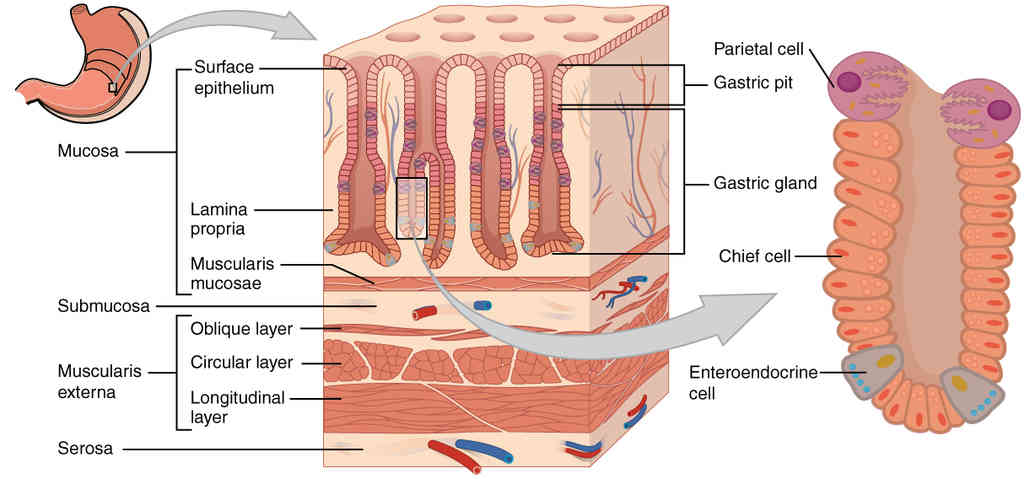

This page is under construction. For now, it is just a resource of the images found in the OpenStax Anatomy and Physiology Handbook. It wil slowly change into a revision tool. Each slide has a number. Use this to refer to the slide. When completed, it will have an unlabelled section, with labelled slides in parallel. On the unlabelled slides, write your answer and use the labelled slide to assess yourself. Keep track by also noting the number on each slide. Improvement at each attempt is important, more so than full marks on a first attempt.